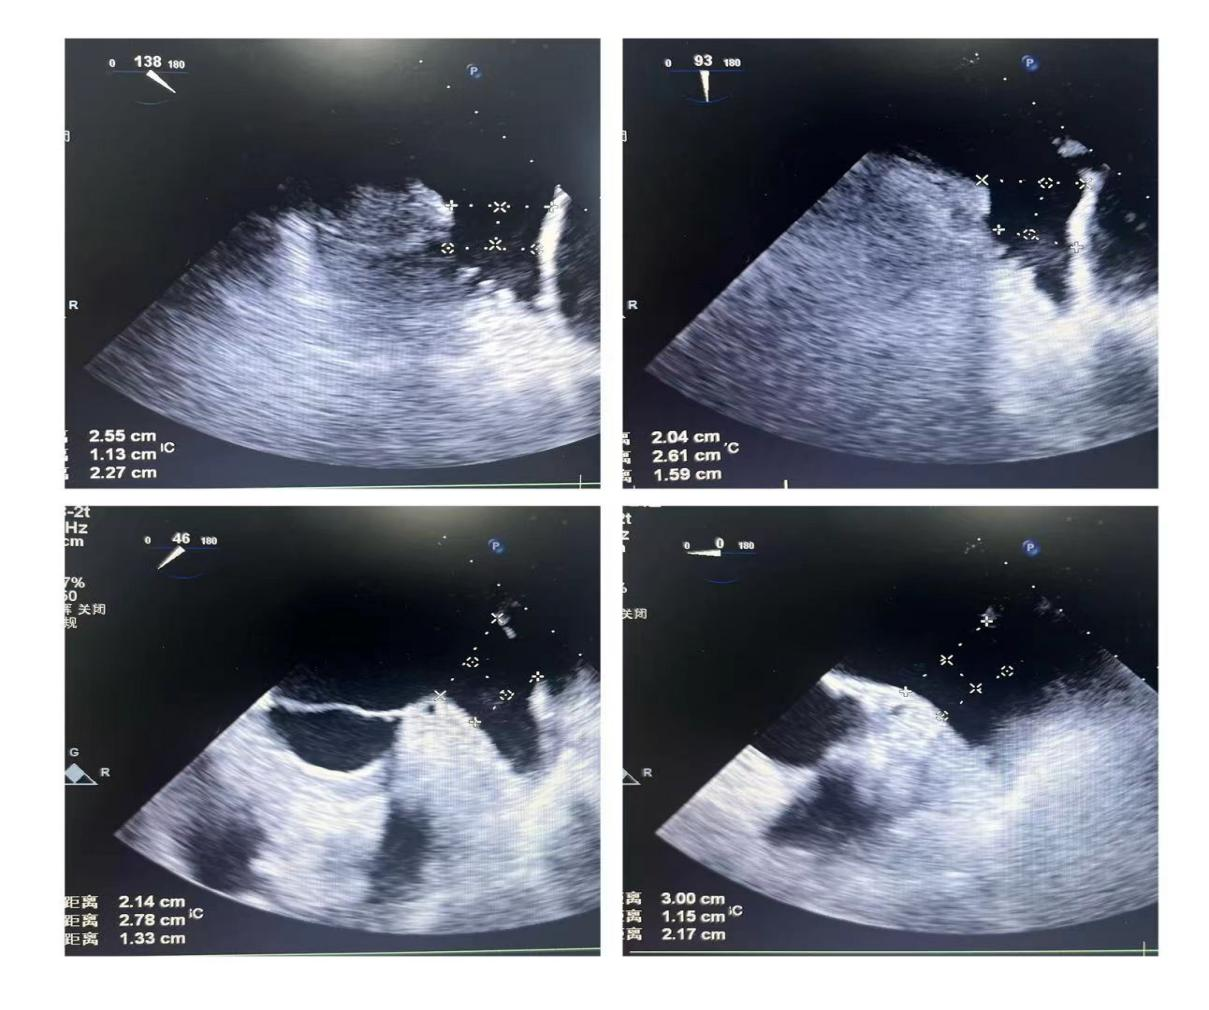

潘教授通过食道超声从4个不同的角度来观察患者左心耳的形态情况,显示心耳为反鸡翅型,位置较低,锚定区为23mm,封堵区为26mm。术者结合多年的临床经验,最终选用型号为LT-LAA-2632的LAmbre™左心耳封堵器对患者进行封堵。

▲(图:通过超声观察进行穿刺)

在食道超声引导下进行房间隔穿刺,由于心耳为反鸡翅型,穿刺位点需靠下靠前,潘教授先在90度双腔切面将定位靠下,再在45度主动脉短轴切面将定位靠前。穿刺成功后上导丝交换J9集团国际LAnavi™分段控弯导引系统送至心耳口部,经过A、B双弯的调整使得鞘管轴向与心耳同轴,获得理想封堵位置。然后推送钢缆释放出固定盘,锚定后退鞘释放出封堵盘。超声下观察贴合良好,无明显残余分流,牵拉测试稳定,即释放左心耳封堵器。释放后再次通过超声各个角度进行验证,封堵结果完美有效,整个过程一气呵成,手术取得了极大的成功。

牵拉测试稳定 完美有效封堵